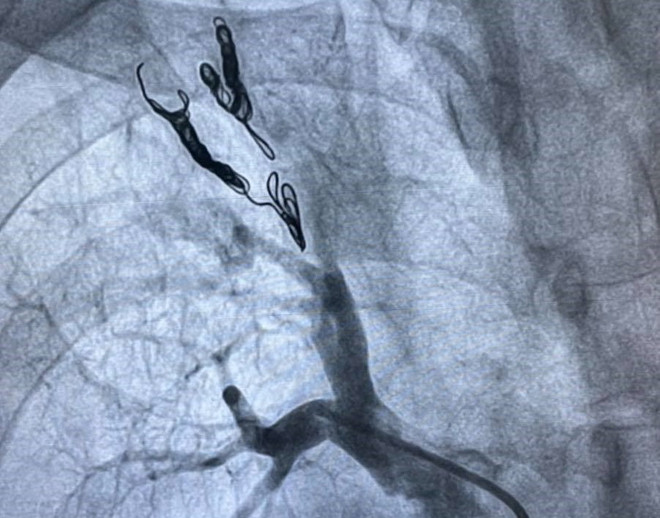

Bệnh viện TW Huế cứu sống bệnh nhân lao phổi ho ra máu, dễ tử vong ảnh 2Hình ảnh trên máy DSA chụp phổi bệnh nhân trước khi được can thiệp tim mạch. (Ảnh: TTXVN phát)

Chiều 13/8, dưới sự chỉ đạo trực tiếp của Giáo sư Phạm Như Hiệp - Giám đốc Bệnh viện Trung ương Huế, các bác sỹ chuyên khoa tim mạch can thiệp, can thiệp mạch não và hồi sức tim mạch đã phối hợp, tiến hành can thiệp bít thành công hai nhánh động mạch thùy trên phổi phải bằng coil (vòng xoắn kim loại).

Sau khi hội chẩn đa chuyên khoa, gồm: hồi sức cấp cứu, ngoại lồng ngực tim mạch, can thiệp tim mạch, X-quang can thiệp và nội soi phế quản, Ban Giám đốc bệnh viện đã quyết định can thiệp nút động mạch phổi qua đường tim.

Theo Tiến sỹ Hồ Anh Bình, Trưởng khoa Cấp cứu tim mạch can thiệp, điều đặc biệt ở trường hợp này là ekip đã can thiệp thành công các nhánh động mạch phổi qua đường tim để đảm bảo các nhánh động mạch phổi bị dò đều được bít hết, giảm thiểu nguy cơ tái phát ho ra máu sau can thiệp.